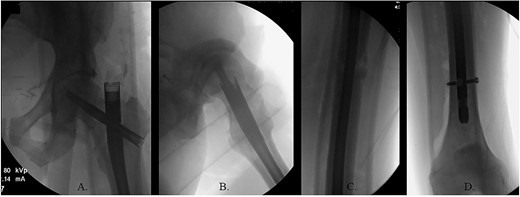

(A) Canulated cutter tool creating a new path in the proximal femur; (B) rigid canulated reduction rod directing the guidewire across a reduced fracture held with a proximal bone hook and distal ball spike pusher; (C) center positioned ball-tipped guidewire at the knee on the AP XR; (D) center positioned ball-tipped guidewire at the knee on the lateral XR.

The ball-tipped guidewire was extracted, and a sharp cannulated cutter created a novel path in the proximal segment (Fig. 4A). A rigid nonunion reamer (DePuy Synthes©, Raynham, MA) was advanced to widen the canal. Closed reduction was lost and so a lateral incision was made at the level of the fracture and a percutaneous reduction was achieved through use of a proximal bone hook and distal ball spike pusher (Fig. 4B).

The hip was extended, and a ball-tipped guidewire was successfully passed across the fracture site to a center–center positionwithin the canal at the level of the knee (Fig. 4C and D). Sequential 0.5-mm reaming from 9 to 13 mm prepared for an 11 × 400 mm, 125° Gamma3® intertrochanteric rod (Stryker© Kalamazoo, MI), with a 95-mm cephalomedullary screw and ×2 distal lateral to medial interlocking 5.0-mm screws (Fig. 5A–D). Through the course of the procedure, 400 cc of blood loss necessitated two units of packed red blood cells.